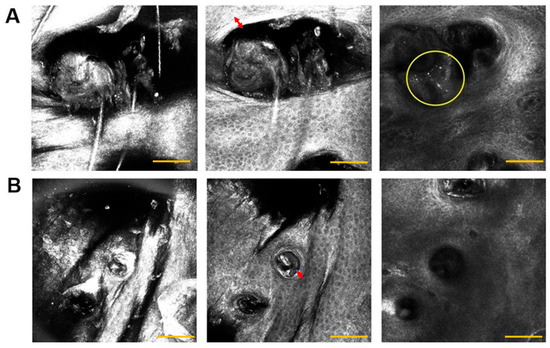

To estimate the morphological features related to the pilosebaceous units in skin acne, we evaluated the presence, shape, and edge of the comedones; the presence of internal amorphous; and the presence of inflammatory infiltrate in the RCM images. The illustrative images are presented in Figure 5.

Figure 5.

Pilosebaceous unit RCM images from participants showing the SC (left), SG (middle), and UD (right), respectively. The images in (A) represent the dysmorphic alterations in the pilosebaceous units. The thick edge (red arrow) and the presence of inflammatory infiltrate in the UD (yellow circle) are presented. The image in (B) is a representation of a comedone with a regular shape, which can also present a thick edge (red arrow); however, the shape is circular and the smaller size is well-delimited, without inflammatory infiltrate observed. Scale bar is 100 µm.

After the application of the formulation, we observed that all groups had the same proportions of pilosebaceous units with regular and dysmorphic shapes at the initial time (T0). However, after 90 days, the 4EO and nanoemulsion groups showed the most favorable results as they reduced the number of pilosebaceous units with dysmorphic shape and decreased the number of altered pilosebaceous units (Table 1).

A reduction in hyperkeratinization was observed in all groups, with a decrease in the number of pilosebaceous units with thick edges and an increase in the number of units with thinner edges. Additionally, all groups exhibited a reduction in the number of units with internal amorphous material and an increase in the absence of internal amorphous material. However, the results for the placebo group were not statistically significant compared to those for the other groups (Table 1). Initially, all images with dysmorphic pilosebaceous units showed inflammatory infiltrates in the UD region. After 90 days, only the placebo group displayed infiltrated lesions in some images. No spongiosis was observed.